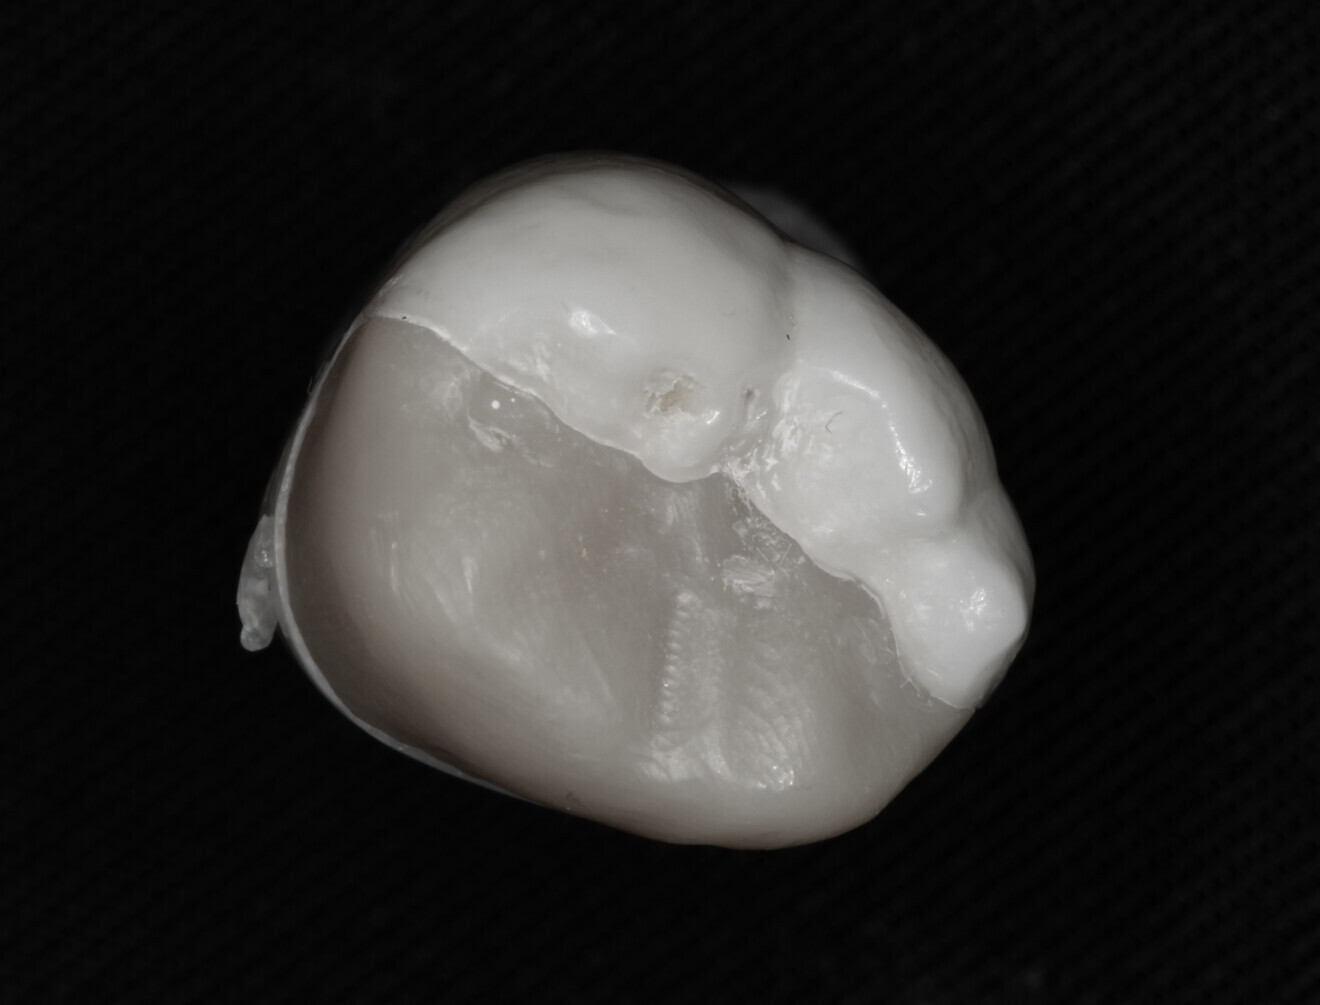

Fig. 7: Cemented onlay.

Fig. 8: Cemented onlay.